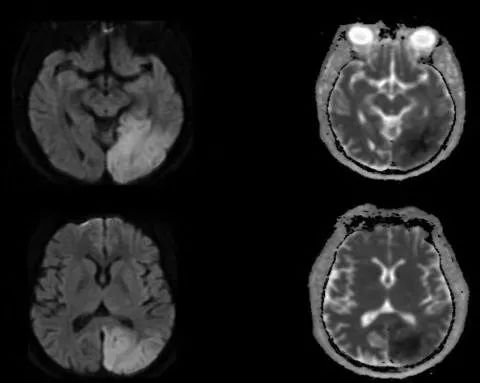

患者,25岁男性,右手电击样感觉和力弱5年。入院查体:右手大小鱼际肌无力,扬鞭征阳性。辅助检查:维生素B12浓度正常。重金属砷、汞、铅浓度正常。颈椎MRI图A、B。经颈椎前路融合术6月后患者右手活动性明显好转。复查颈椎MRI见图C。

答案:平山病

颈椎MRI常规扫描T2WI示颈椎C4-C6椎体水平颈髓形态变细,其内可见纵行长T2信号影,在过屈位(flexional position)磁共振,可以清楚地看到下颈后部硬膜之往前位移而压迫到颈髓。上述是平山病影像特点。平山病是一种少见的局灶性缺血性颈脊髓灰质病,其确切的发病率和患病率不清。主要影响青少年男性,被认为是由颈髓腹侧运动神经元的动态机械损伤或缺血性损伤引起。1959年由Hirayama首先报道。常隐袭起病,表现为一侧手部肌肉的无力和萎缩,肌萎缩局限在手和前臂肌肉,多单侧受累,常无脑神经症状,无锥体束征,无大小便障碍。颈部过屈位MRI扫描多可明确诊断。